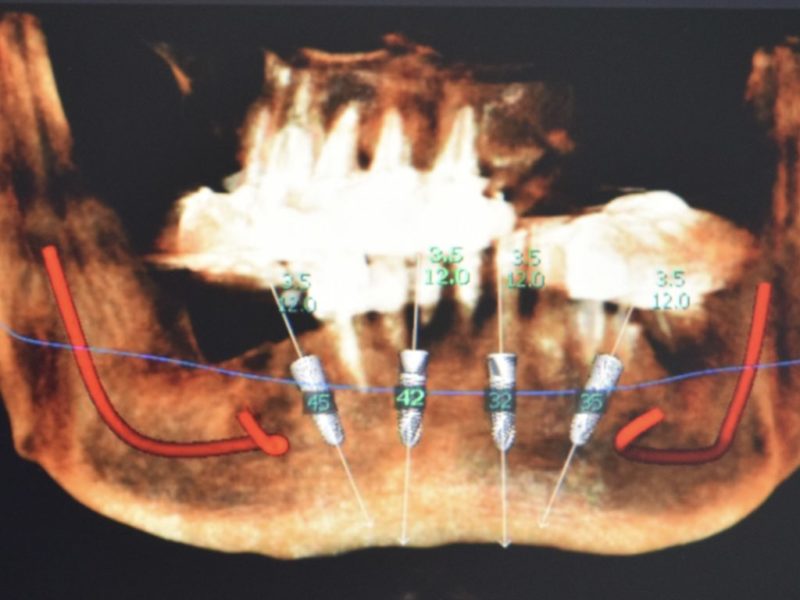

The use of an arch to help praparing the ostheotomy in terms of inclination and positioning can be a great option to easily define the correct positionin for an all on four concept. This patient came with the request of stabilizing his own prosthesis so the treatment plan included the insertion of 4 implants on which we will use the suitable straight and angulated MUA to stabilize a retentive bar to retain a duplicate of the pre-existing prosthesis.

During the surgical session the preparation of the implant sites was made with the help of the guide arch that have to be inserted in the medial area and gives the indication on the correct positioning of implants for an all on four or all on six concept prosthesis. To minimize the tissue trauma we inseted the implants with a flapless surgery and with the use of stops to determine precisely also the lenght of the preparation. Right after the surgery the patient was left with healing screws on top of the implant and with his previous denture which we hollowed internally to avoid trauma on the implants. After 5 months the patient came back we took an impression an made a duplicate of the prosthesis which we used to build the bar to fix on top of MUAs and an internal framework and the retentive caps.

The guide allows to easily determine the inclination of the preparating tools but this also helps also the choice of the angled MUA. During the second session we simpli inserted the Multi unit abutments and fixed the prosthetic bar with the proper screws before trying and checking the occlusion of the definitive prosthesis.